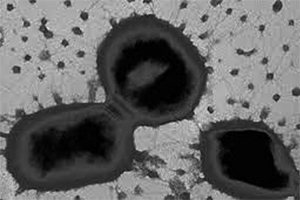

Відомо, що у порожнині рота (ПР) налічується <700 видів бактерій, більшість з яких становить резидентну флору, яка стабілізує біоплівку ПР. Водночас підвищення рівня резидентної мікрофлори призводить до набуття нею вірулентності, а отже, зростання розвитку запальних процесів. До пародонтопатогенів належить близько 20 видів бактерій, які за ступенем вірулентності розподіляють на дві групи. До 1-ї групи належать бактерії, прямо пов’язані із прогресуванням захворювання, а до 2-ї групи — бактерії, що відіграють другорядну роль у розвитку захворювань пародонта. Porphyromonas gingivalis (P. gingivalis) належать саме до 1-ї групи (рисунок).

P. gingivalis є важливою патогенною бактерією, яка опосередковує місцевий запальний процес у пародонті з подальшою її адгезією та проникненням у глибші структурні елементи пародонта. При цьому відбувається порушення нормального фізіологічного метаболізму та пригнічення активації апоптозу протеаз, які належать до потенційних факторів ризику розвитку раку. Розвиток неопластичних процесів ШКТ характеризується високим ступенем коморбідності та смертності на тлі незадовільного рівня ранньої діагностики та високої вартості лікування. P. gingivalis, що виявляється у пародонтальних кишенях, є грамнегативним облігатним анаеробом, здатним експресувати специфічні фактори вірулентності, включаючи триходерму, гінгіпаїни, білок послідовності тетратрикопептидного повтору, позаклітинні полісахариди, систему поглинання гемоглобіну, ліпополісахариди тощо. Коактивація гінгіпаїнів із ліпополісахаридами впливає на порушення функцій імунного захисту тканин пародонта та спричиняє розвиток запалення, деструкцію періодонта і кістки.